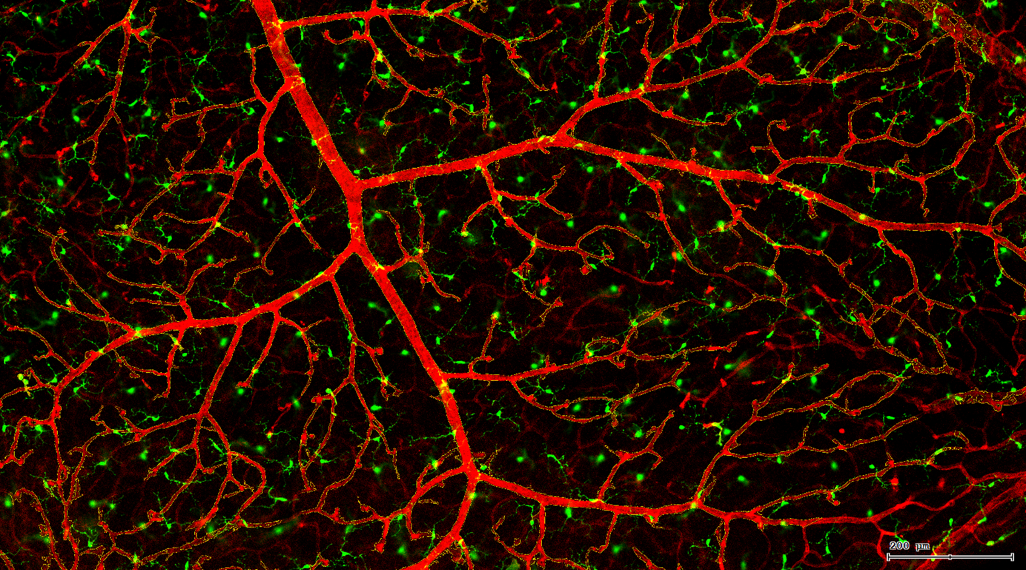

视网膜是眼球中最重要的结构之一,它是位于眼球壁最内层的一层透明薄膜,周围布满了大量的感光细胞和神经纤维,通过它可以直接接受来自外界环境的光线并在眼球内形成影像,通过神经纤维将影像信息传送至大脑中枢形成视觉。

其它中枢神经系统内也有小胶质细胞,在健康的视网膜中,神经元和小胶质细胞之间的交流对维持神经元向大脑发送信号的能力非常重要。

视网膜血管作为人体内唯一可以进行非创伤直接观察的深层微血管,其生理状况的检查对高血压、糖尿病、动脉硬化等心血管疾病的诊断、治疗评价具有重要意义。

一般而言,眼底图像通常都是通过激光扫描成像进行采集,但是由于眼底可观测的视野往往是很有限的,一个患者的眼底信息需要多张扫描图像才能完全显示出来。这种局限性大大不利于病情进行全面的、细致的诊断。Tissue Cytometry全景组织流式定量分析技术进行全景图像获取,在单细胞、组织结构、细胞空间信息等多个层面进行定位、定性、定量分析。从而更好的对病变区域进行有针对性的跟踪观察和全面分析。

视网膜荧光样本中小胶质细胞胞体、神经纤维识别、血管识别、血管斑点识别、神经元与血管的距离分析。

1. 利用TissueFAXS系统进行玻片荧光的全景扫描。

3. 根据FITC通道识别神经胞体并筛选出有效细胞胞体(细胞核识别算法)。

根据染色强度,染色面积,细胞形态学,利用正反向回溯功能和设门圈选Gating,排除杂质,细胞碎片,黏连细胞(绿色框线标记),获得有效的神经元胞体,(粉色框线标记),并将胞体按照面积分为两类(散点图)。

由于该视网膜样本是标记的小胶质细胞,根据面积将神经胞体分为两类(Small bodycell,Big bodycell),反向回溯Big bodycell中的细胞后,应用Input Gate功能筛选短粗的神经纤维,作为激活态的小胶质细胞。

激活态小胶质细胞识别